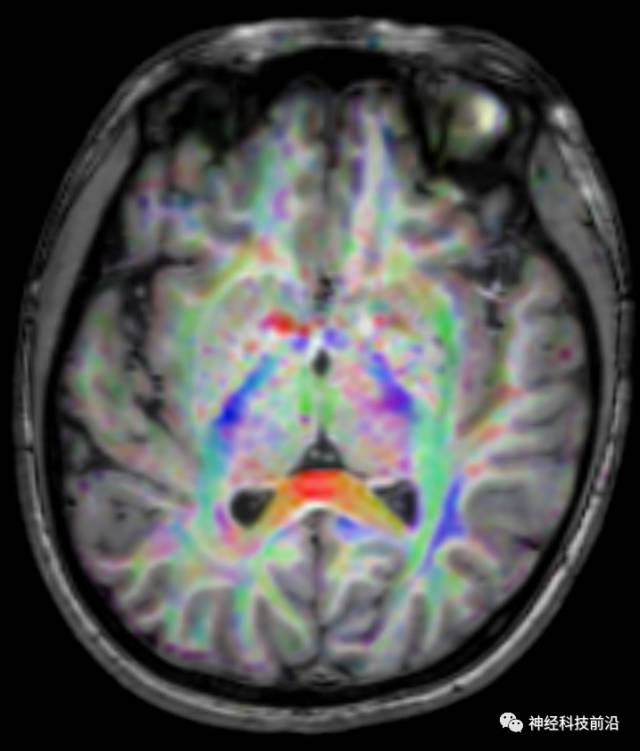

脑干内高信号为一近环形纤维束,其作用尚待研究。

终上所述:脑干高信号为一近环形纤维束,内囊后肢高信号为皮质脑桥束,皮质脊髓束在中脑位置略靠后。高信号位于中脑前缘,是皮质脑桥束的位置所在,另外有部分桥连纤维。